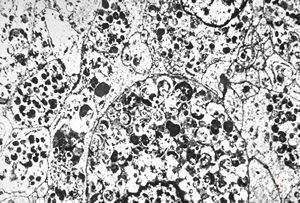

F, 7y. | molluscum contagiosum … virions